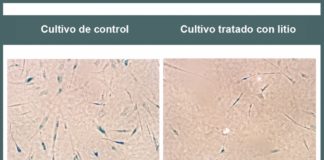

Comienza a revelarse el efecto beneficioso del litio en ancianos con...

Resultados de experimentos realizados en células cerebrales humanas y en ratones sugieren que este medicamento retarda el envejecimiento celular, uno de los factores relacionados...